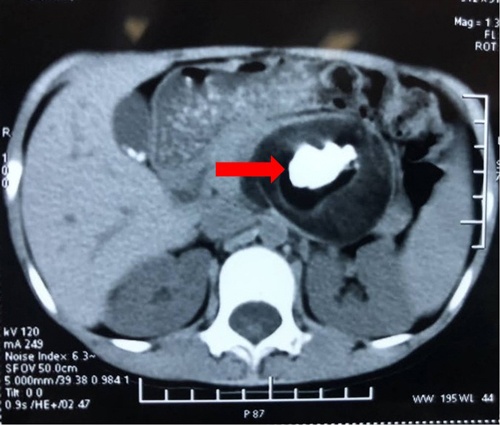

Các bác sĩ tại Bệnh viện Bãi Cháy (Quảng Ninh) vừa thực hiện kỹ thuật nội soi mật tụy ngược dòng (ERCP) gắp giun đũa dài 25 cm trong ống mật chủ của nam bệnh nhân V.A.C. (31 tuổi, ở Yên Bái).

Trước đó, sau khi nhập viện, siêu âm, chụp X-quang, bệnh nhân được chẩn đoán bị giun đường mật.

Trong quá trình nội soi, các bác sĩ cắt cơ oddi và dùng bóng kéo khảo sát từ ống gan chung xuống tá tràng để gắp giun ra ngoài. Sau đó, bệnh nhân được bơm rửa lại đường mật. Hiện tại, tình trạng người bệnh ổn định, không còn đau bụng và có thể xuất viện sau 24 giờ theo dõi.